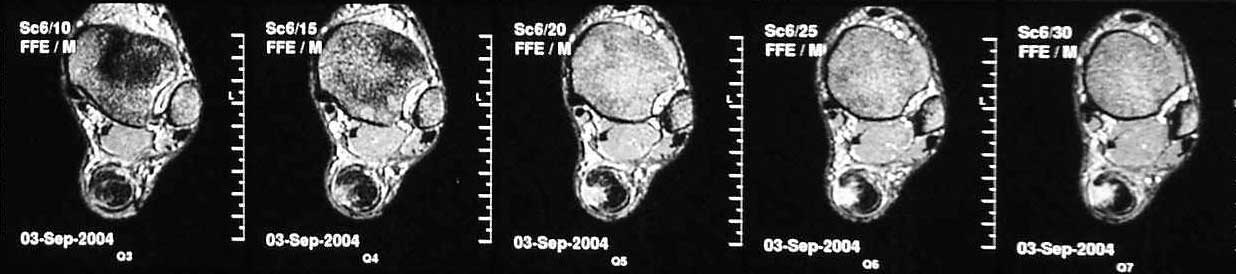

В сентябре сделана МРТ, цитирую заключение: "по внутренней поврехности сухожилия на уровне средней трети определяется очаг с неоднородной гиперинтенсивностью сигнала на T2W и изоинтенсивного сигнала T1W неправильной форму. Прротяженность очага до 43 мм в вертикальном диаметере. В центральной части очага на протяжении до 22 мм определяется прерыв и диастаз волокон ахиллова сухожилия. Заключение: Частичный дегенеративный разрыв ахиллова сухожилия, тендинит".